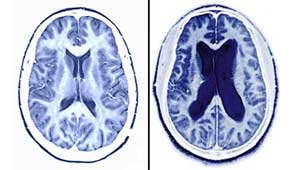

2.大脑性共济失调 额桥束和颞枕桥束是大脑额、颞、枕叶与小脑半球的联系纤维,病损可引起共济失调,症状轻,较少伴发眼震。